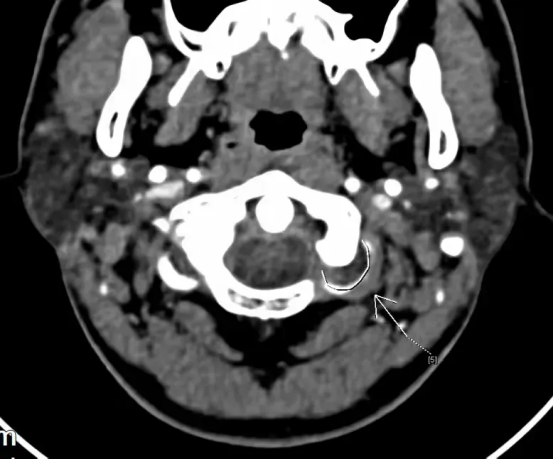

图为患者的头颈联合CTA,考虑左椎动脉V3段夹层伴附壁血栓形成

为进一步明确夹层的位置、长度以及血流情况并进一步治疗,脑五科团队为患者进行脑血管造影检查明确为椎动脉夹层,血流良好,不需要血管内治疗。经积极抗凝等治疗,宋先生头晕及双下肢无力等症状基本消失。